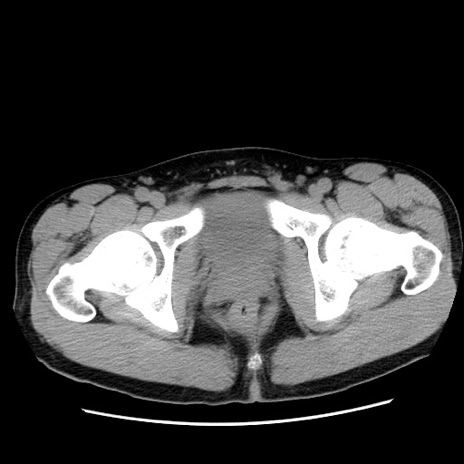

症例36(横断像)

【症例】20歳代 男性

【主訴】心窩部痛

【現病歴】今朝より上腹部痛あり。一旦軽快していたが再度出現したため救急要請。昨日夕に白身の魚を含む刺身を食べた。

【身体所見】BP 136/89mmHg、HR 74/min、BT 37.0℃、腹部:膨満、軟、心窩部に圧痛あり。反跳痛なし、筋性防御なし、腸雑音やや亢進あり。

【データ】WBC 17700、CRP 0.48